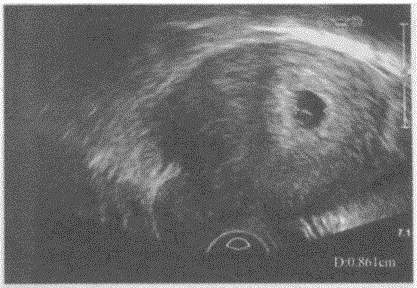

临床资料:女,25岁,自诉停经38天。超声综合描述:经阴道扫查子宫后位,形态饱满,肌层回声均匀,宫腔内见1.7cm×1.2cm×0.9cm孕囊,内见卵...

问题 临床资料:女,25岁,自诉停经38天。 超声综合描述:经阴道扫查子宫后位,形态饱满,肌层回声均匀,宫腔内见1.7cm×1.2cm×0.9cm孕囊,内见卵黄囊,未见胎芽及胎心搏动。 超声提示: